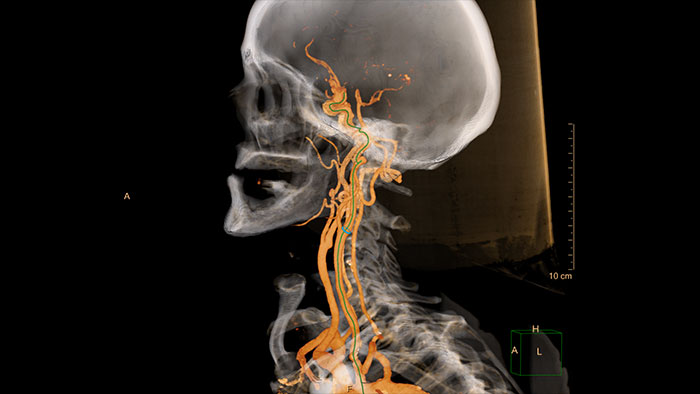

Advanced Vessel Analysis (AVA)

Multi Modality Advanced Vessel Analysis (AVA)

Comprehensive vascular analysis planning

Designed to examine and quantify different types of vascular lesions from CTA and MRA scans. It accommodates different modes of inspection, allows labeling different vascular lesions, and helps navigating through multiple findings.

Demonstrated to reduce the post-processing time by 50% when compared to manual Head & Neck CT angiography (CTA) analysis*.

Benefits

• Ability to choose which Head & Neck Bone Removal method to be used (Standard vs. Smooth).

• Customizable Volume rendering “smoothness” for the 3D Head & Neck vascular structure using a smoothness control.

* Ardley N et al. Efficacy of a new post processing workflow for CTA head and neck. ECR 2013 / C-1760.